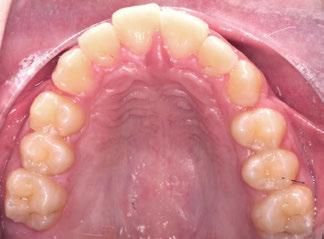

Ciencia y clínica Rehabilitación 100% digital: desde la planificación a la carga

Presentamos el tratamiento rehabilitador de una paciente, realizado íntegramente en una sesión. Para este caso se ha utilizado un protocolo quirúrgico digital y guiado mediante la Plataforma de Planificación Bego Guide. Asimismo, se ha diseñado digitalmente una prótesis de carga inmediata atornillada e impresa con resina Bego VarseoSmile TriniQ®. Por lo tanto, se trata de un caso cuyo tratamiento precisa diferentes fases, pero efectuadas, todas ellas, el mismo día. De forma sencilla y cómoda para la paciente y el odontólogo, se ha obtenido una rehabilitación fija, funcional y estética. Palabras clave: Cirugía guiada, implantología oral guiada, cirugía sin colgajo, férula quirúrgica, rehabilitación fija maxilar, impresión digital, escáner intraoral, implantes dentales.

Ejecución técnica protésica

aproximadamente una hora y media. Usamos resina Bego VarseoSmile TriniQ® para puentes definitivos. Aunque en este caso la vamos a usar para confeccionar unas prótesis fijas atornilladas provisionales de larga duración, dado al aumento de dimensión vertical que vamos a realizar a la paciente, de esta forma obtendremos una neuroprogramación de la ATM reinstaurando una Dimensión Vertical apropiada y mejorando la estética facial de la paciente. Excluimos de la carga aquellos implantes que no obtuvieron una estabilidad primaria superior a 35 N/ cm2. El material permite la realización de una carga inmediata en material definitivo en puentes (Figuras 31 a 38).

CONCLUSIONES

• La cirugía con técnica guiada disminuye drásticamente el rango de desviación de los implantes dentales y permite una colocación tridimensional óptima, respetando el espacio de confort y bajo el concepto de Implantología protésicamente guiada.

• La cirugía guiada, en combinación con la impresión 3D, permite la confección protésica el mismo día de la intervención, siempre y cuando se obtenga estabilidad primaria.

• De forma sencilla y cómoda para la paciente y el odontólogo, se obtiene una rehabilitación fija, funcional y estética.